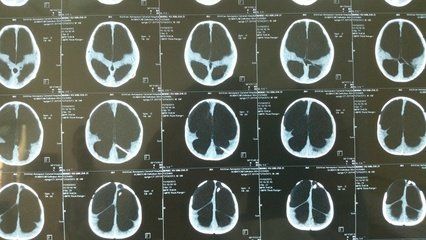

脑积水严重了会怎么样?

脑积水如果出现了恶化,患者可能会出现意识下降、昏迷不醒,另外患者还可以出现大小便失禁、走路不稳以及智力低下等情况,严重的患者可能会导致患者出现死亡。

脑积水有很多种分类方法,比较常见的有交通性脑积水、梗阻性脑积水、急性脑积水以及慢性脑积水等。

脑积水是一种临床症状,通常是由多种疾病导致的继发性脑损害。在临床上脑积水通常可以分为两大类。